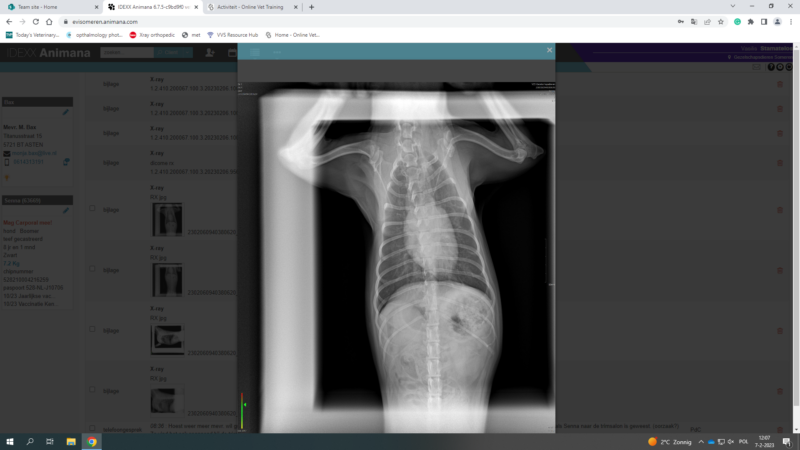

these are the photos of the bloodwork and from the ultrasound

This post is about a patient of mine that came to me on Wednesday.

General information and history: Cat, male, not castrated, 11 years old with different behaviour since 3 days. According with the owners, the cat didnt want to eat and drink for 3 days. Also he wasnt active and he was hiding. The owners didnt have…